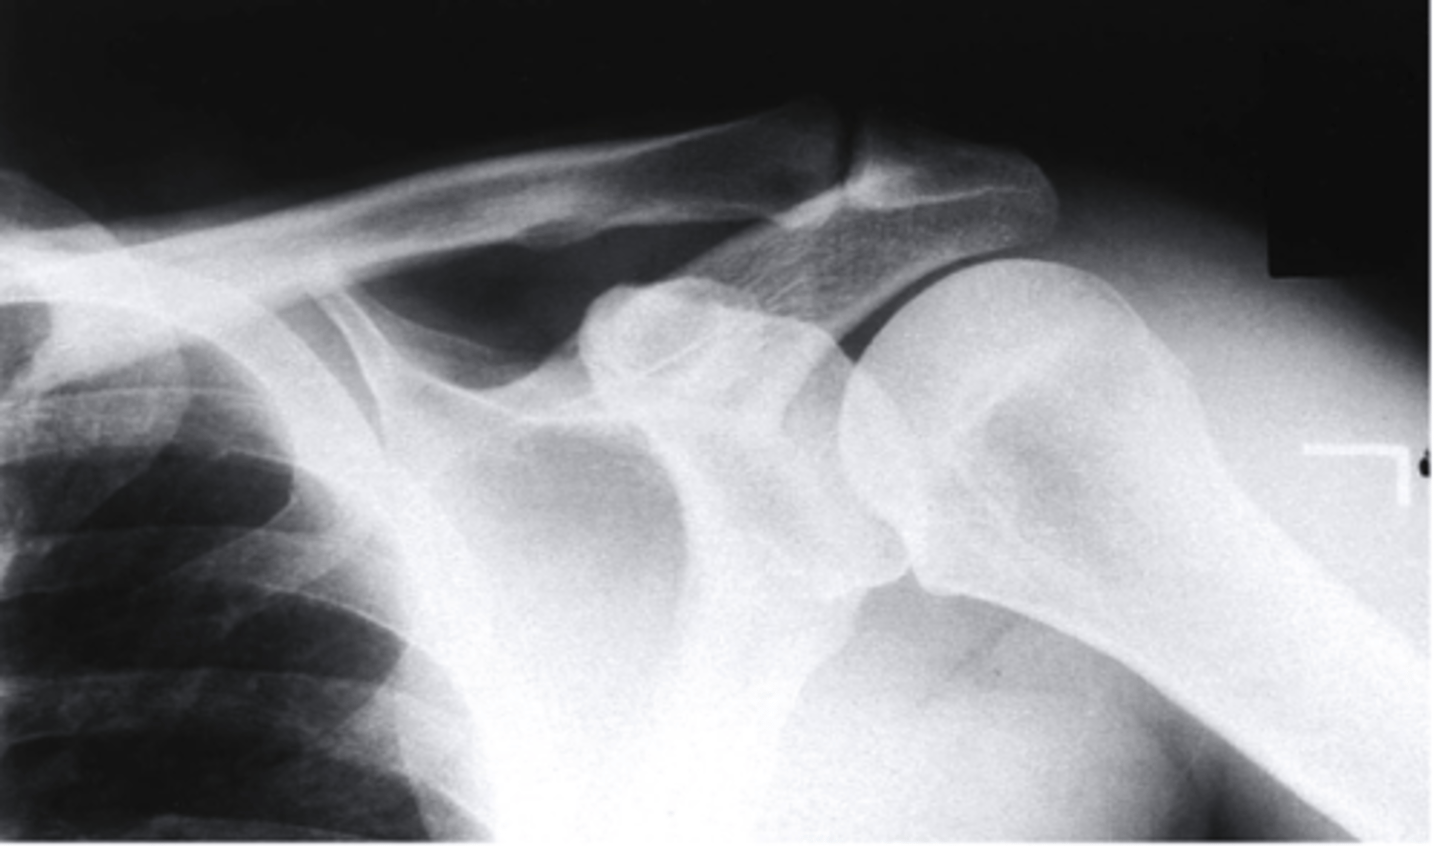

scapular Y lateral

what view is this

clavicle

what does the pink line point to?

coracoid process

acromion of scapula

humeral head

inferior angle of scapula

body of scapula